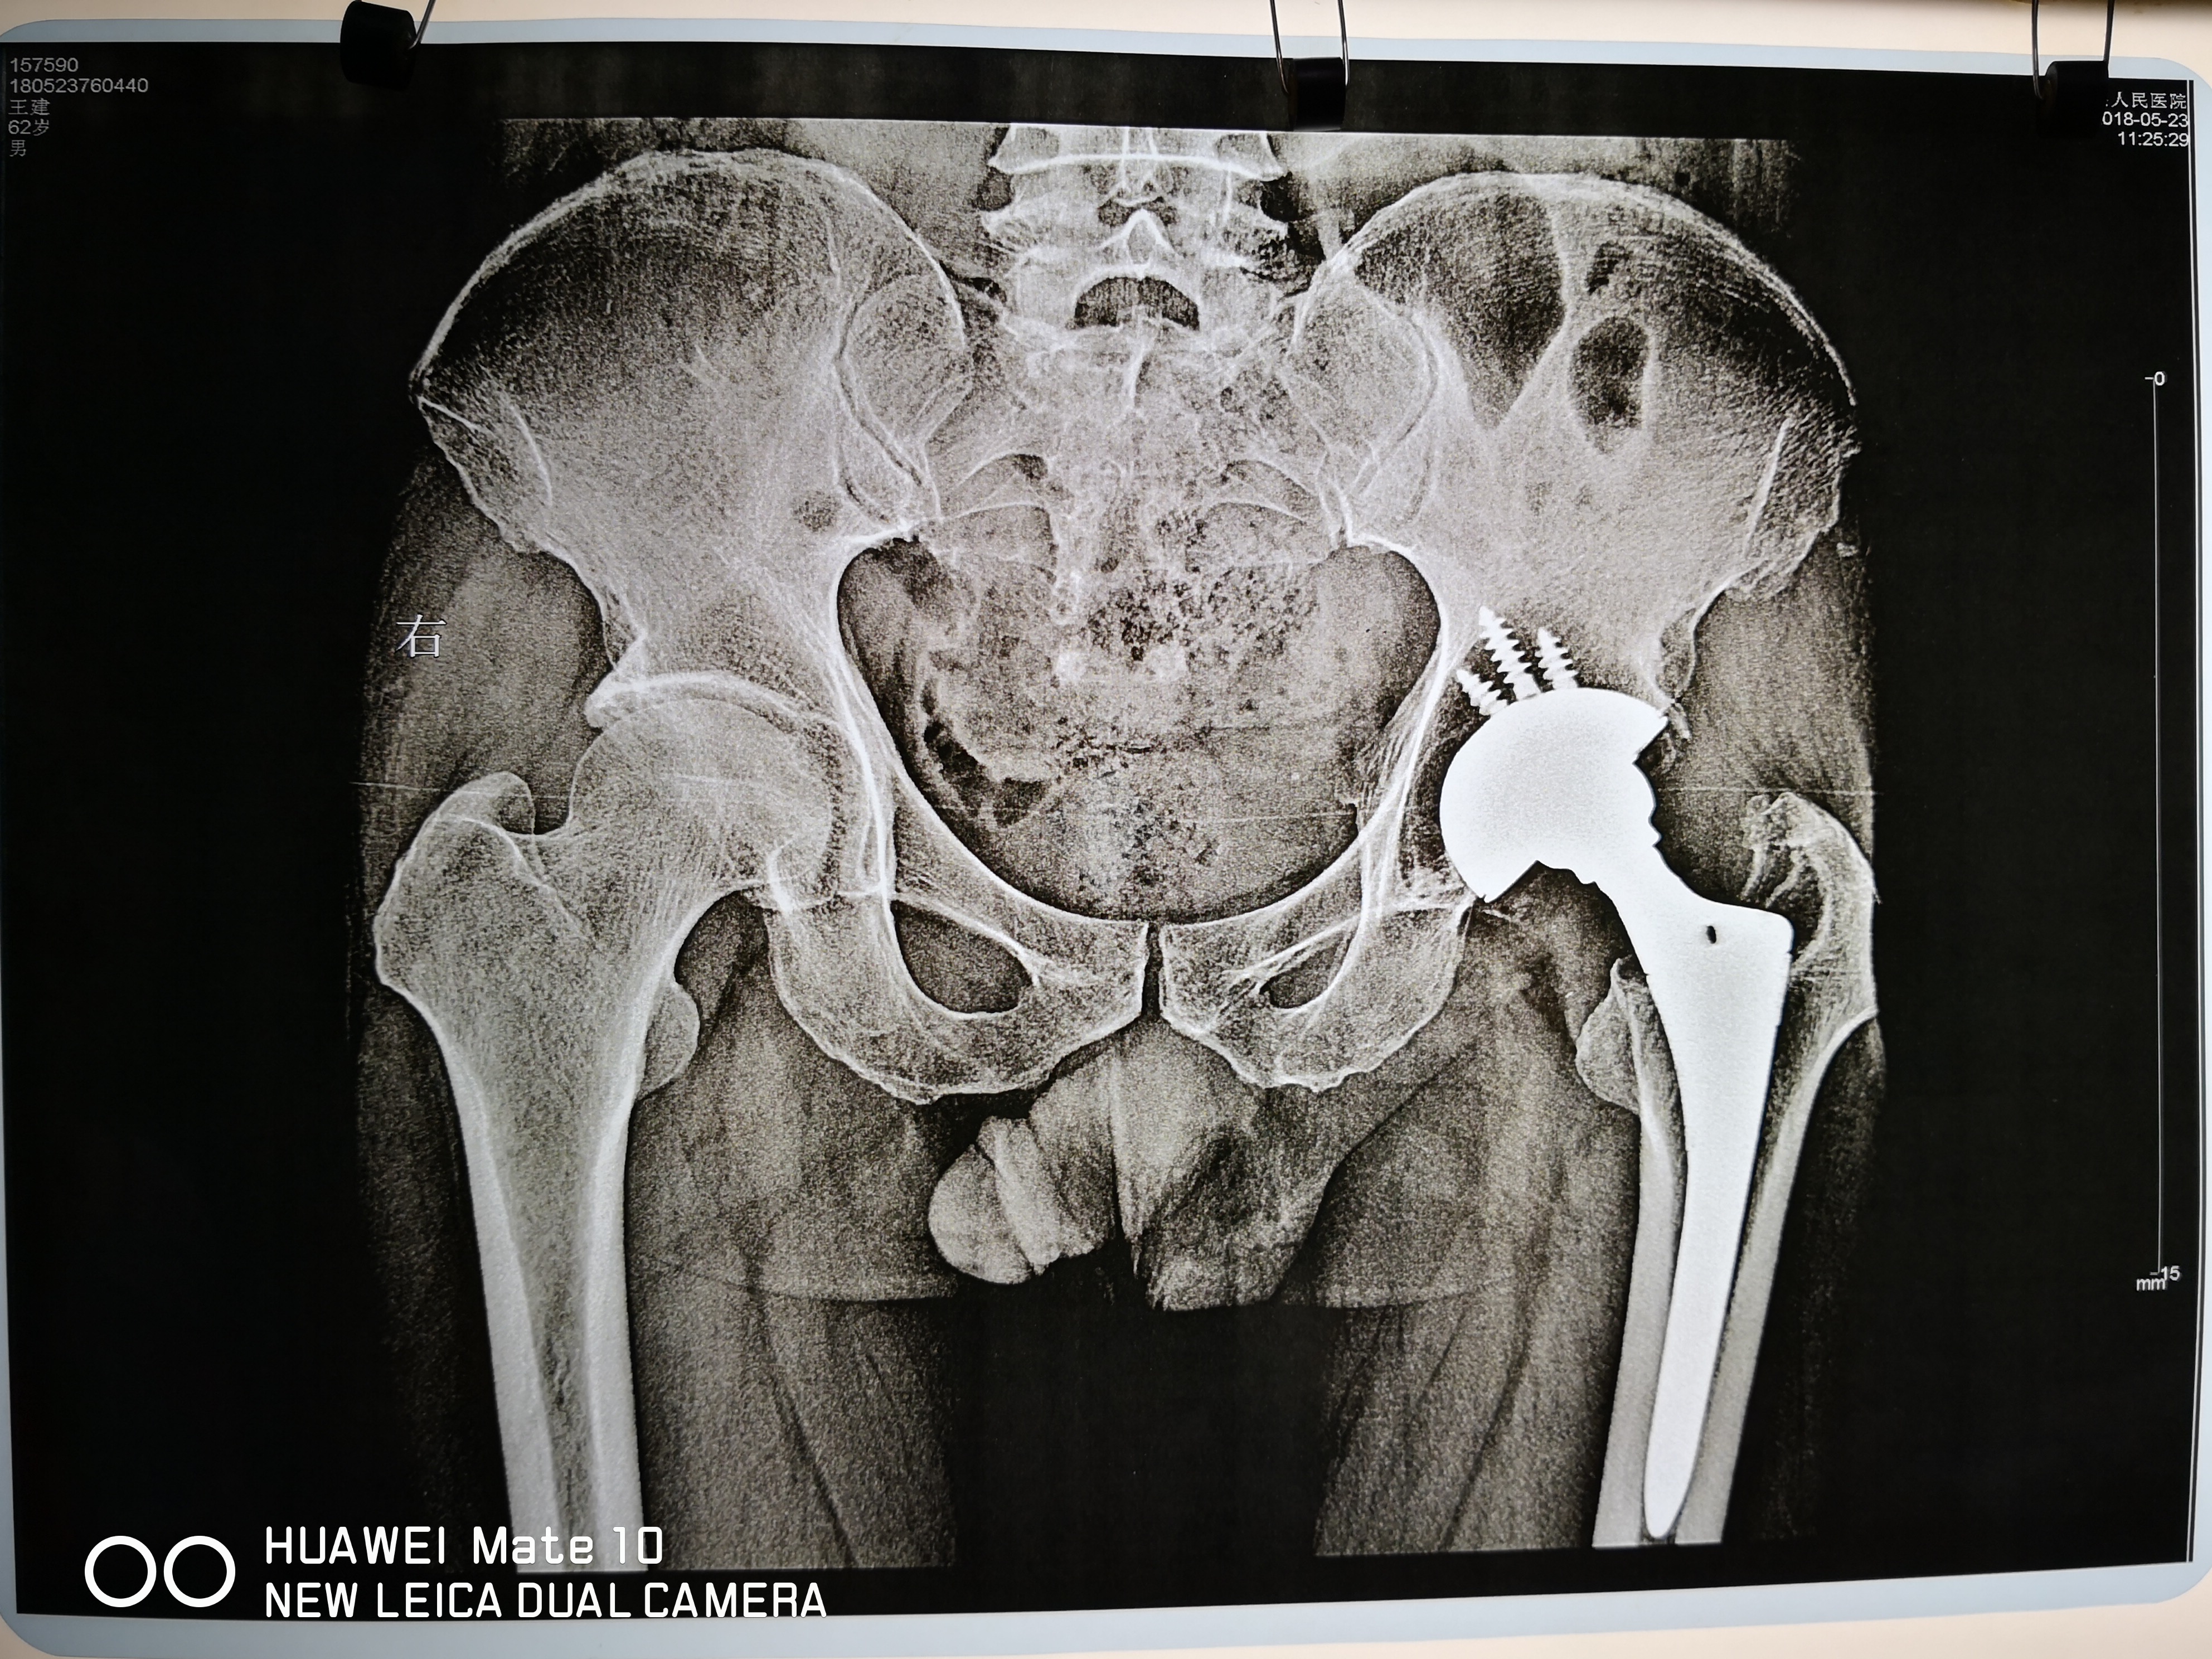

这位来自遵义市的患者,因十五年前不慎患有左侧股骨头坏死,经当地某医院行股骨头坏死置换术,多年来,各方面都不错。但因时间飞逝,现在从X片看,置换部位出现骨质疏松,钙流失严重。其潜在的风险就是再次置换新的一个股骨头。